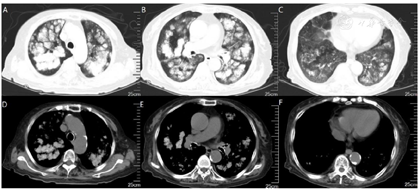

钙离子(我院2020年12月17日):3.91mmol/L。钙离子(我院2021年4月17日):3.5mmol/,多次复查钙离子明显升高。血气分析(2021年4月22日未吸氧):PH 7.48,PaCO2 37mmHg,PaO2 58mmHg,HCO3-:27.6mmol/L,BE 4.1mmol/L,Lac 1.6mmol/L,K+ 4.1mmol/L,THbc 84g/L。骨代谢六项:降钙素3.87pg/ml,甲状旁腺素46.00pg/mL,β-胶原降解产物2.480ng/mL,总I型胶原氨基端延长肽315.000ng/mL,骨钙素47.700ng/mL,25羟维生素D 4.700ng/ml;甲功八项:甲状腺过氧化物酶抗体(ATPO) 10.80U/ml,甲状腺球蛋白抗体(ATG)>4000U/mL,甲状腺球蛋白(TG) 0.20ng/ml,三碘甲腺原氨酸(TT3) 1.30nmol/L,甲状腺素(TT4) 46.80nmol/L,游离T3(FT3) 2.48pmol/L,游离T4(FT4) 6.69pmol/L,高灵敏促甲状腺素(TSH) 9.470mIu/L;肿瘤标志物全套(女):肿瘤相关抗原125(CA125) 52.70U/ml,肿瘤相关抗原153(CA15-3) 31.90U/ml,细胞角蛋白19片段(Cyfra211) 2.78ng/ml,异常凝血酶原(PIVKA-Ⅱ) 32.700mAU/ml,β2-微球蛋白(β2-MG) 3.04μg/mL,人绒毛膜促性腺激素(HCG) 7.54mlU/ml,绝经前ROMA值(Pre-ROMA) 97.19%,绝经后ROMA值(Post-ROMA) 81.68%,胃泌素释放肽前体(ProGRP) 279.0pg/ml。胸部平扫CT(我院2020年12月18日图1):右肺中叶及左肺下叶结节,右肺钙化灶。气管及主支气管管壁钙化。胸部平扫CT(我院,2021年4月19日图2):两肺见弥漫性、松散性沿支气管及血管分布的结节状及团片状高密度影,以两肺上叶为著,呈对称性改变,纵隔窗大部分病灶已实变,CT值约为100HU。胸部增强CT(我院,2021年4月25日):两肺见弥漫性、松散性沿支气管及血管分布的团絮状、棉花团样密度增高影及磨玻璃密度影,以两肺上叶为著,呈对称性改变,纵隔窗大部分病灶已实变,CT值约为100HU,增强扫描动脉期CT值约127HU,静脉期CT值约111HU。诊断提示:两肺代谢性疾病,考虑转移性肺钙化。PET/CT提示双肺改变考虑非肿瘤性病变,不除外肺泡蛋白沉积症可能,建议相关检查。电子支气管镜检查,镜下未见明显异常(图3),肺泡灌洗液色清亮。右肺上叶灌洗液送检脱落细胞回报示标本内见噬细胞、偶见上皮细胞,未见到恶性细胞。灌洗液病原微生物宏基因检测回报示白色念珠菌(序列数:4091)、光滑念珠菌(序列数:726)、EB病毒(序列数:33)。2021年5月11日行CT引导下经皮肺穿刺活检(图4),于右肺上叶穿刺获得2条约2.3cm长暗红色肺组织,送检肺组织常规病理及病原微生物宏基因检测。病理回报示(右肺上叶)肺泡结构破坏,肺间质纤维母细胞增生,有淋巴细胞、浆细胞浸润,其内见网络样钙化,局部见有机化及玻璃样变,并见有增生的肺泡上皮,细胞有异型,胞浆嗜酸,考虑为反应性增生,病变形态不能除外转移性钙化引起的弥漫性肺泡损伤性病变,请结合临床(图5)。肺组织病原微生物宏基因检测回报示白色念珠菌(序列数:1)、EB病毒(序列数:1)。全身骨显像示双肺弥漫性高密度伴放射性浓聚,考虑转移性钙化,结合临床资料,首先考虑肺泡微石症,肿瘤性疾病待排。甲状旁腺显像未见明显异常。

本病例存在以下两个特点:1.肺部影像学表现重,双肺多发高密度影,沿支气管及血管分布,以两肺上叶为著,小叶中心分布为主,部分存在实变。具有且弥漫性、对称性的特点。2.对比2020年12月17日及2021年4月19日两次胸部平扫CT,可见肺部影像学快速进展,但咳嗽、咳痰及活动后呼吸困难症状较前未见明显加重。入院后高度怀疑原发肺癌或转移性肺癌,考虑到患者81岁,心肺功能差,建议患者完善PET/CT密切病变性质,结果回报示双肺改变考虑非肿瘤性病变,不除外肺泡蛋白沉积症可能。胸部增强CT及全身骨扫描考虑转移性肺钙化。笔者认为病理是诊断转移性肺钙化的金标准,遂利用呼吸介入手段尽早行肺活检。患者81岁,存在I型呼吸衰竭,心功能欠佳,对气管镜操作医生要求极高。我中心呼吸内镜医生完成气管镜常规检查及肺泡灌洗后,患者出现血氧降低,未能通过气管镜获得肺活检标本。气管镜灌洗液病原微生物高通量测序提示白色念珠菌、光滑念珠菌、EB病毒感染,但不考虑引发此影像学改变。后续通过CT引导下经皮肺穿刺活检获得病理,病理结果不除外转移性钙化。综合患者病史,胸部增强CT、全身骨显像及病理结果,可明确诊断为转移性肺钙化,但病因尚不明确。患者无透析、器官移植病史,甲状旁腺功能及甲状旁腺显像未见明显异常,可除外原发性或继发性甲状旁腺功能亢进。患者既往因肌酐升高,4个月前于我院诊断为慢性肾脏病,但本次入院多次复查肾功能均为正常。根据骨代谢六项结果,及血钙、血磷趋势,不支持为慢性肾脏病所致转移性钙化。因患者年龄较大,给予降低血钙后,血钙维持在正常范围内,症状较前缓解,建议患者出院观察,定期复查胸部CT及钙离子。